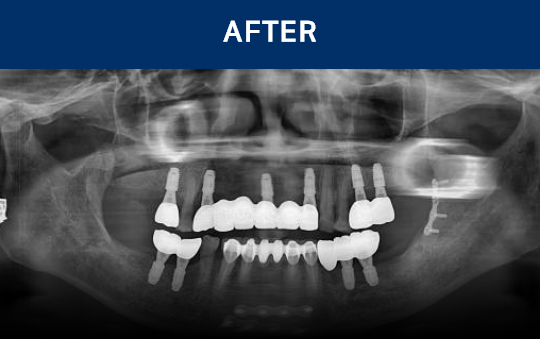

전후가 명확한 결과, 그 결과가

곧 신길플란트치과의 신뢰입니다.

불편함 없이 웃고, 걱정 없이 드실 수 있도록 임플란트로 일상의 편안함을 되찾아드리겠습니다.